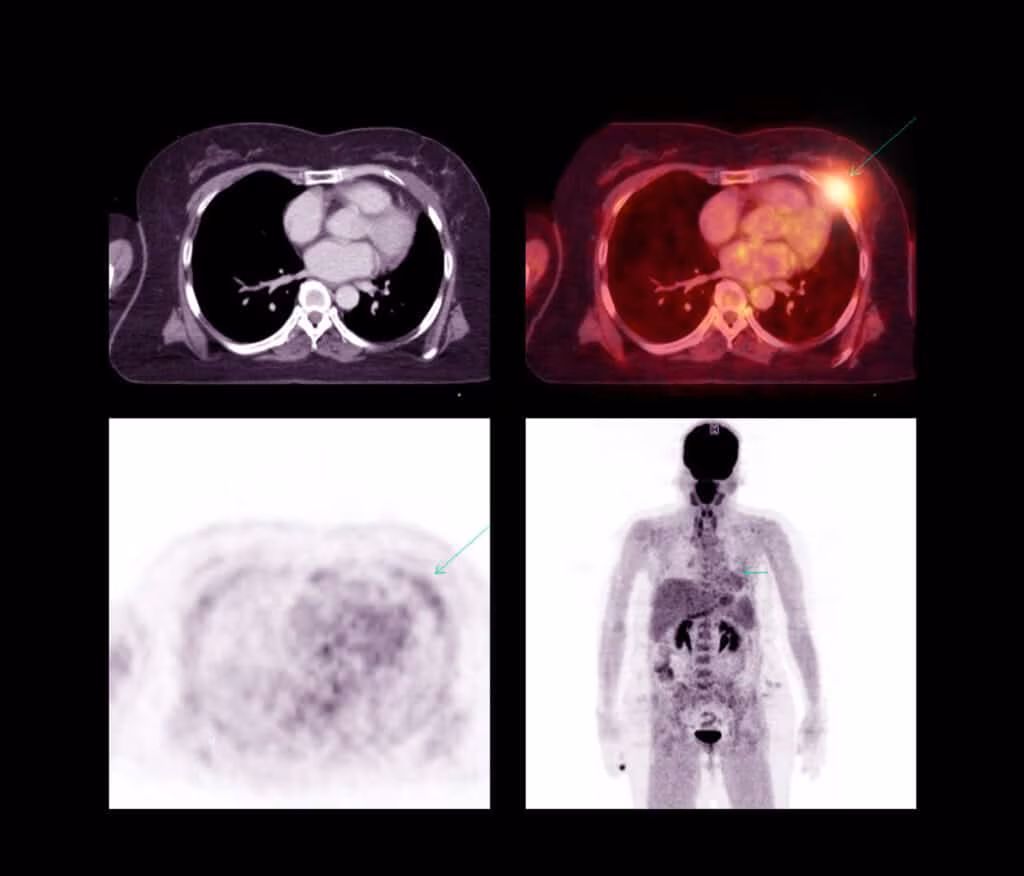

Poiché la tomografia a emissione di positroni presenta problemi legati alla risoluzione, è unita alla TC. In passato, prima si eseguiva prima una tecnica e poi l’altra, ma si rischiava di cadere in una serie di errori tra i quali il paziente per entrambi gli esami doveva mantenere la stessa posizione per evitare la presenza di falsi positivi. Inoltre nella TC viene adoperato un lettino piatto, invece la PET utilizza un lettino curvo, facendo così assumere il paziente una differente posizione. Per risolvere tali problemi nascono i tomografi ibridi, che ha portato ad un miglioramento in termini di accuratezza nell’interpretazione di immagini del corpo e degli organi. Tramite l’unione delle due tecniche diagnostiche si ottengono bioimmagini che contengono informazioni sia anatomiche, con la TC, e sia funzionali per la presenza della PET.

Nonostante la TAC e la PET possano trovarsi nello stesso strumento, entrambi possono essere eseguite da sole, presentando alcune differenze: la TAC si avvale dell’utilizzo di radiazioni ionizzanti cioè i raggi X che attraversano l’organismo e ne permettono di ottenere l’immagine, invece la PET adopera un radiofarmaco il quale emette positroni β+ direttamente dall’organismo. Inoltre, la TAC permette di ottenere bioimmagini di carattere morfologico, invece la tomografia a emissioni di positroni dà come risultato immagini funzionali.

L’acquisizione total body è adoperata per lo studio approfondito di differenti tipologie tumorali e riguarda l’acquisizione di tutto il corpo. L’acquisizione statica interessa una regione specifica del corpo, quella dinamica permette di comprendere l’evolversi dell’accumulo del radiofarmaco. Infine l’acquisizione gated riguarda gli organi interni in movimento come ad esempio il cuore unendo tale imaging a un elettrocardiogramma.